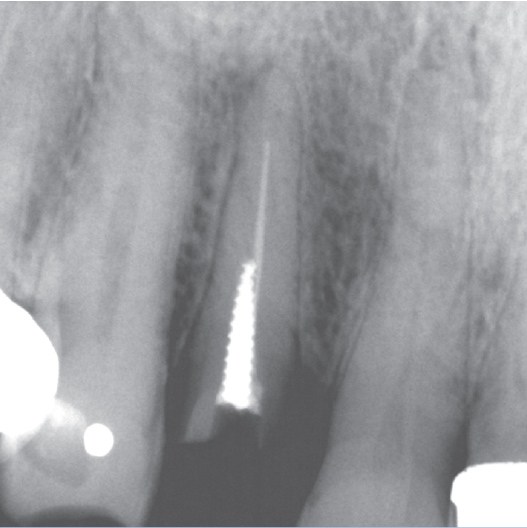

After

After Root Canal treatment